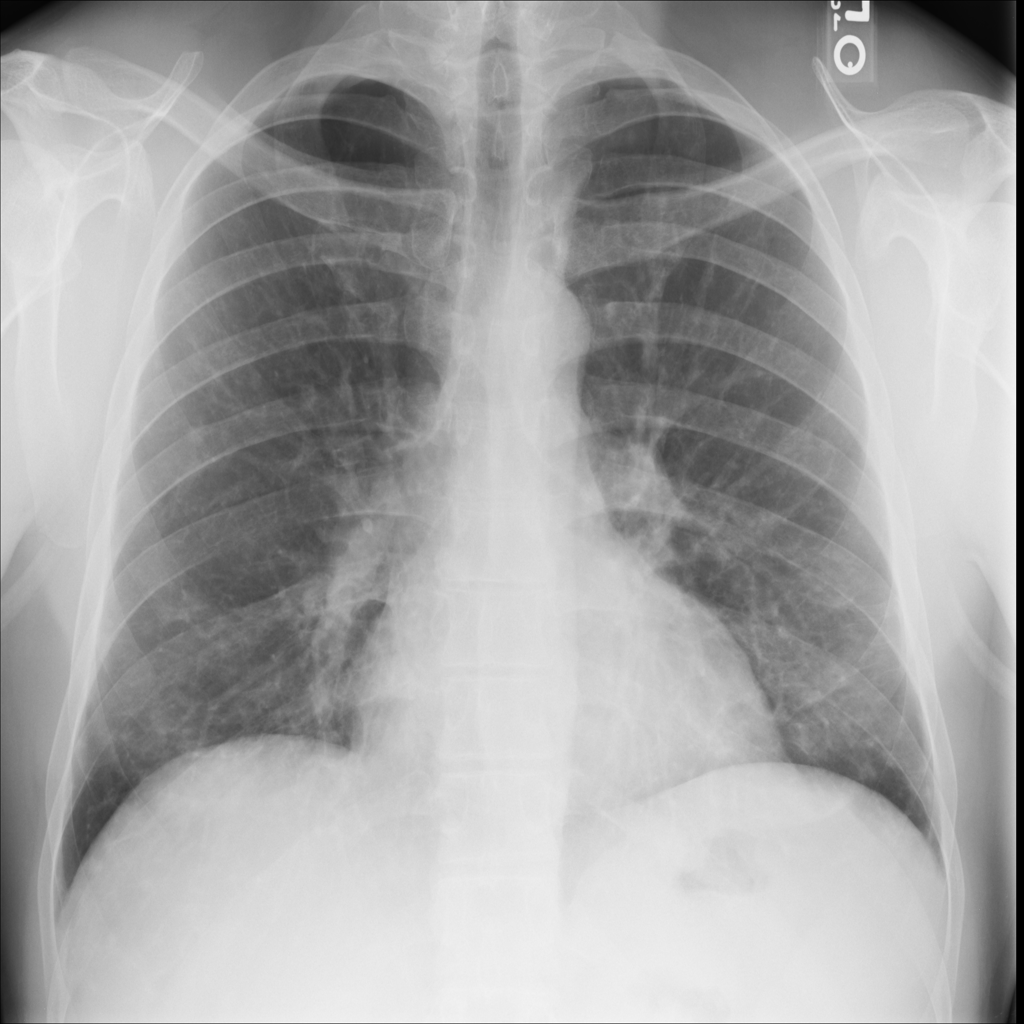

Nodule

A nodule is a small rounded opacity in the lung or chest field. It is a descriptive imaging finding that can be benign or more concerning depending on size, appearance, and context.

Showing up to 90 reference images for Nodule.

PAT-F3E7 · IMG-002Nodule

PAT-F3E7 · IMG-002

PA